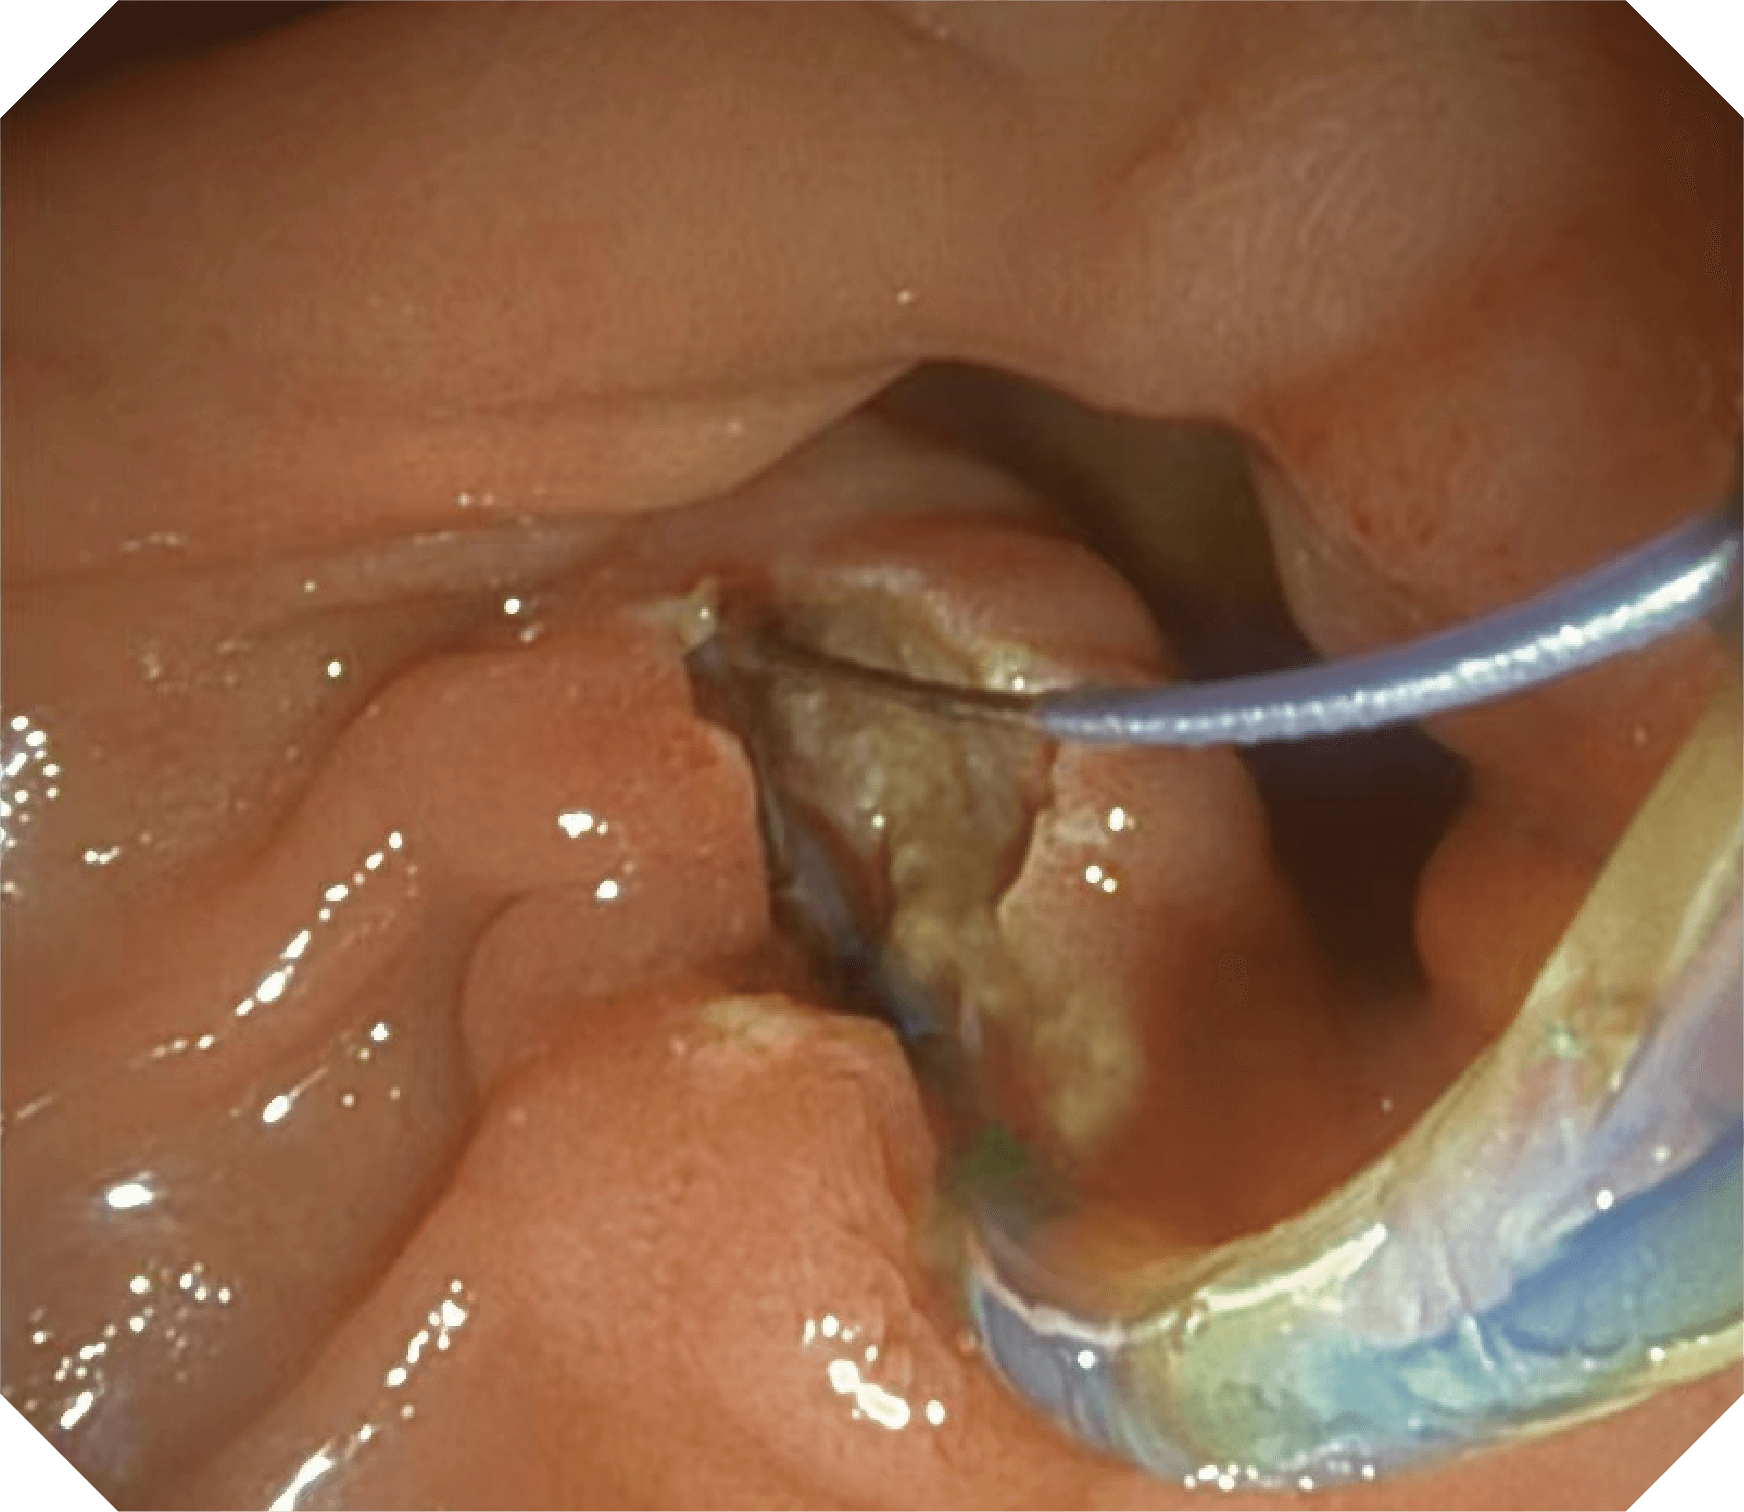

导丝机械锁紧功能

V槽设计提升导丝控制

优异的手术器械抬举性